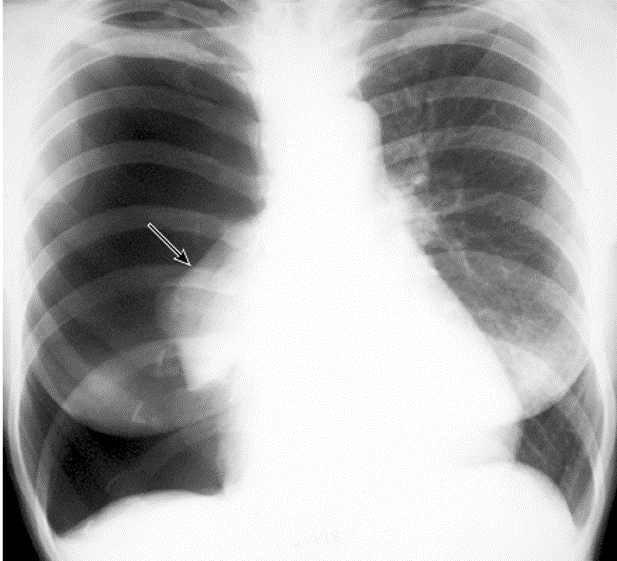

Pleural Effusion

Right sided Pleural Effusion, w/ meniscus sign

Be suspicious of malignancy bc/ large volume